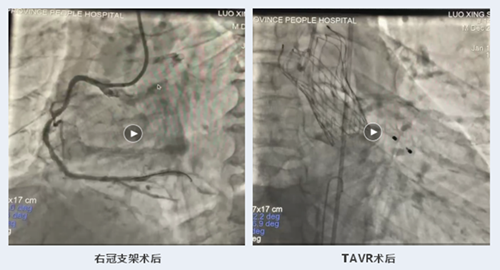

2023年1月11日,在江西省人民医院(南昌医学院第一附属医院)副院长、省心血管病医院院长洪浪的带领下,省心血管病医院四科李林锋主任医师团队成功为1例主动脉瓣重度狭窄合并严重冠心病的高龄患者实施诱导麻醉下“一站式”冠状动脉支架植入+经导管主动脉瓣置换术。

罗大爷今年78岁,因胸闷痛1年,再发加重2天于2022年12月13日转至我院,入院诊断为急性非ST段抬高型心肌梗死,入院后行心脏彩超检查示:主动脉瓣功能性二叶瓣畸形(TypeI型),主动脉瓣退行性变并重度狭窄并轻度关闭不全,左室收缩功能明显减低(LVEF:34%)。12月14日行冠脉造影示:左主干+三支血管严重钙化并狭窄,前降支近段近乎闭塞。考虑罗大爷同时合并主动脉瓣重度狭窄、心功能不全、高血压病、2型糖尿病、慢性肾功能不全等众多基础疾病,外科主动脉瓣置换术+搭桥术风险大,家属拒绝外科。遂先介入处理好“罪犯”血管前降支至左主干病变,择期行导管主动脉瓣置换术(TAVR),同时处理右冠脉病变。众所周知,TAVR的优势是不需要开胸,创伤小,手术时间短,术后恢复快,主要适应症是老年重度主动脉瓣狭窄,尤其是不能耐受外科手术的患者,罗大爷就是TAVR手术的适宜人群。

1月11日中午,在洪浪及李林锋的主刀下,手术有条不紊地进行着。先施行右冠脉PCI术,接着在诱导麻醉状态下实施TAVR手术。整个手术过程顺利,耗时仅1个半小时。术后罗大爷即刻清醒,能自主交谈,听诊主动脉瓣区杂音明显减弱,复查心脏彩超提示主动脉瓣未见明显瓣周漏,心功能明显改善。术后第二天查房,罗大爷自述胸闷痛、气促等症状明显缓解,血压、心率平稳,谈笑风生,容光焕发,5天后康复出院。整个术后天数及手术过程体现了短、平、快,不仅大大缩短住院时间、节省费用,且手术见效快,得到患者及家属的认可,提高了患者满意度。